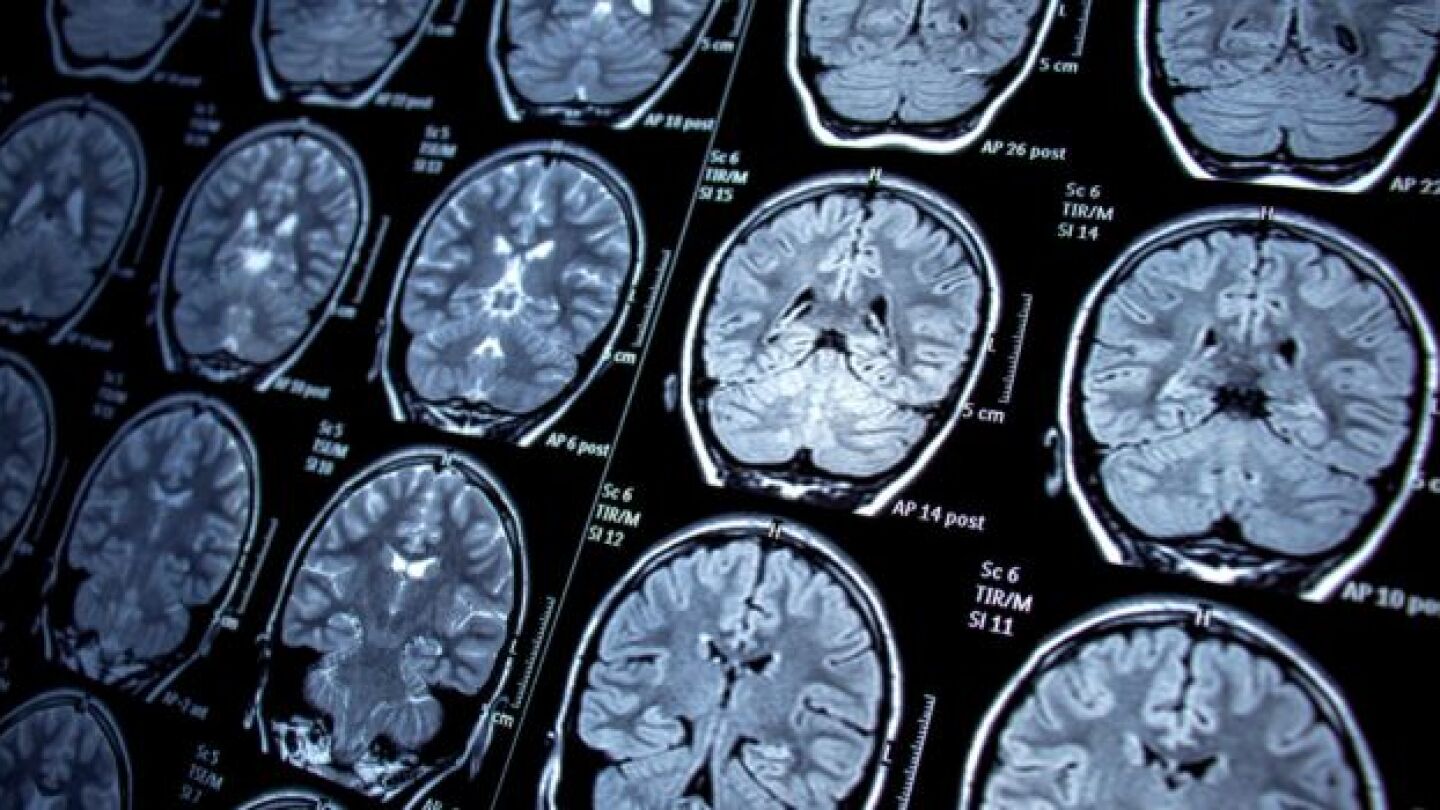

After decades of limited progress—owing to the difficulty of treating the disease and resultant market risk—glioblastoma research is entering a new phase spurred by smarter trials, targeted funding and renewed interest from companies like Merck and Jazz Pharmaceuticals.

Emboldened by technological advances and a deeper knowledge of glioblastoma, Merck, Kazia Therapeutics, CorriXR Therapeutics and others are targeting the often-fatal brain tumor.